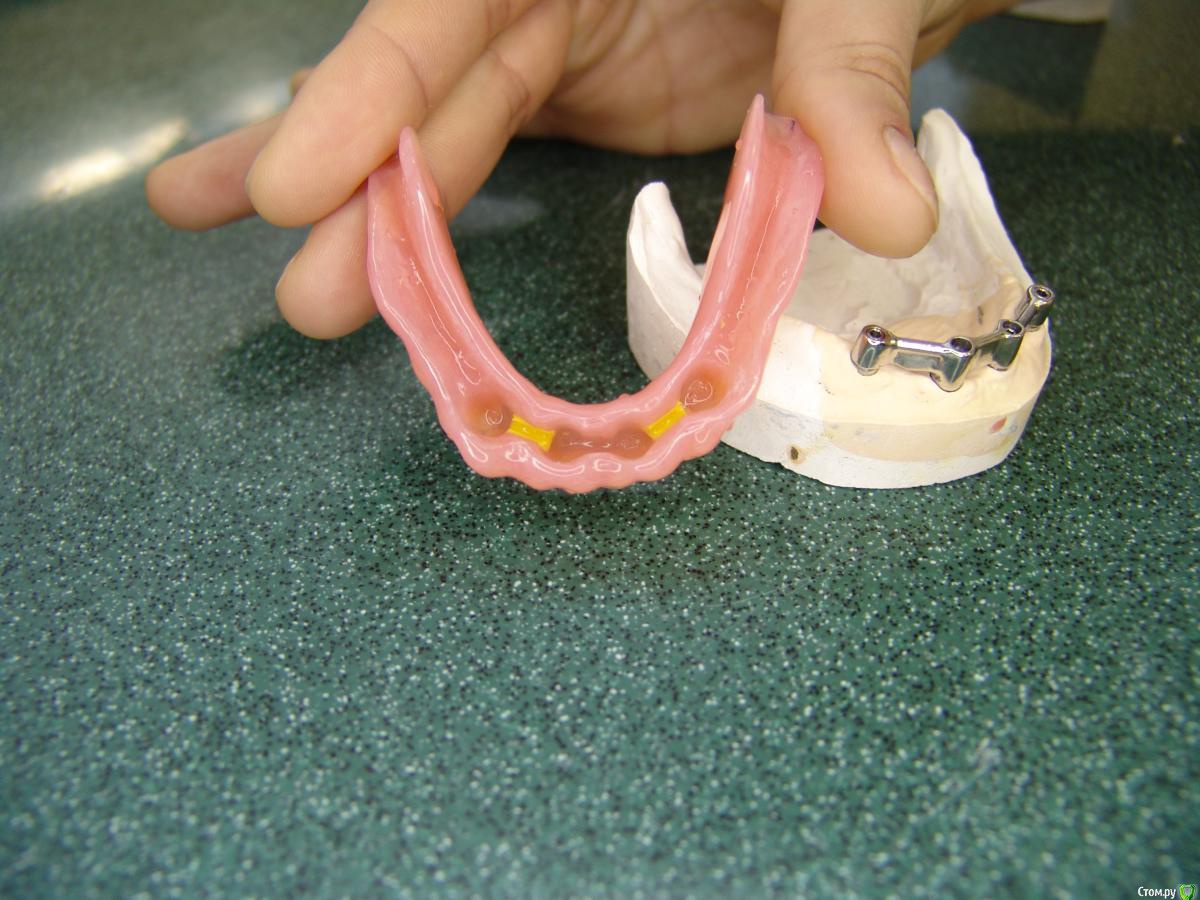

stommm Опубликовано 5 февраля, 2017 Поделиться Опубликовано 5 февраля, 2017 А я бы две балки. Надежно, долговечно, очень хорошо держит и меньше возни с параллельностью.Ну или все на четырех. 2 балки в смыле слева на 2 импланта и справа такую же? Почему бы не одну как показали ниже? В моей практике так делали 1 раз при большом расстоянии между медиальными имплантами наверху Вот уже десять лет ходит и еще столько же проходит. (В те времена у нас еще не было "все на четырех"). 20150302-DSC_9404.jpgДок, замки к балкам не добавляете? Ортопеды с кем работал/работаю делают в основном с замками бредент, один работает только с мк-1, и сейчас с сикуралоками начали работать. Есть у балок без замков преимущества перед балками с замками? По комфорту, долгосрочному прогнозу...Очень интересно ваше мнение. Ссылка на комментарий

Doc Опубликовано 6 февраля, 2017 Поделиться Опубликовано 6 февраля, 2017 2 балки в смыле слева на 2 импланта и справа такую же? Почему бы не одну как показали ниже? В моей практике так делали 1 раз при большом расстоянии между медиальными имплантами наверху Док, замки к балкам не добавляете? Ортопеды с кем работал/работаю делают в основном с замками бредент, один работает только с мк-1, и сейчас с сикуралоками начали работать. Есть у балок без замков преимущества перед балками с замками? По комфорту, долгосрочному прогнозу...Очень интересно ваше мнение. На приведенных фотографиях как раз две балки с матрицами, а посередине просто связано для прочности, в середине нет никаких матриц. Замки не добавляем, ибо не вижу в этом никакой необходимости. Приведенные выше варианты работают более чем достаточно и для прочной фиксации (иногда даже ослаблять приходится, не все могут снять) и для долговечности. Сделал таких протезов не один десяток, до сих пор менял матрицы два-три раза, остальные так и ходят со старыми, все прекрасно держится.Перестал делать такие конструкции только из-за появления "все на четырех". Теперь нет смысла мучаться со съемными, если с тем же количеством можно получить несъемный вариант. 2 Ссылка на комментарий

Doc Опубликовано 6 февраля, 2017 Поделиться Опубликовано 6 февраля, 2017 Док, а перебазировку в таких случиях часто делаете?Когда сдаю протезы, то всегда предупреждаю, что съемная часть делается на 3-5 лет, балка навсегда. На практике же пока что не переделал ни одного. Никто не хочет. Если удается раз в пять лет заманить на контрольный осмотр, то разговор один и тот же: "у меня все в порядке, ничего переделывать не надо". Теоретически кость должна оседать. Но практически, видимо, вся нагрузка идет на балку, десна не сильно перегружена, кость не сильно уходит. В общем, сам не понимаю почему, но переделок была одна-две за последние 10 лет. Ссылка на комментарий